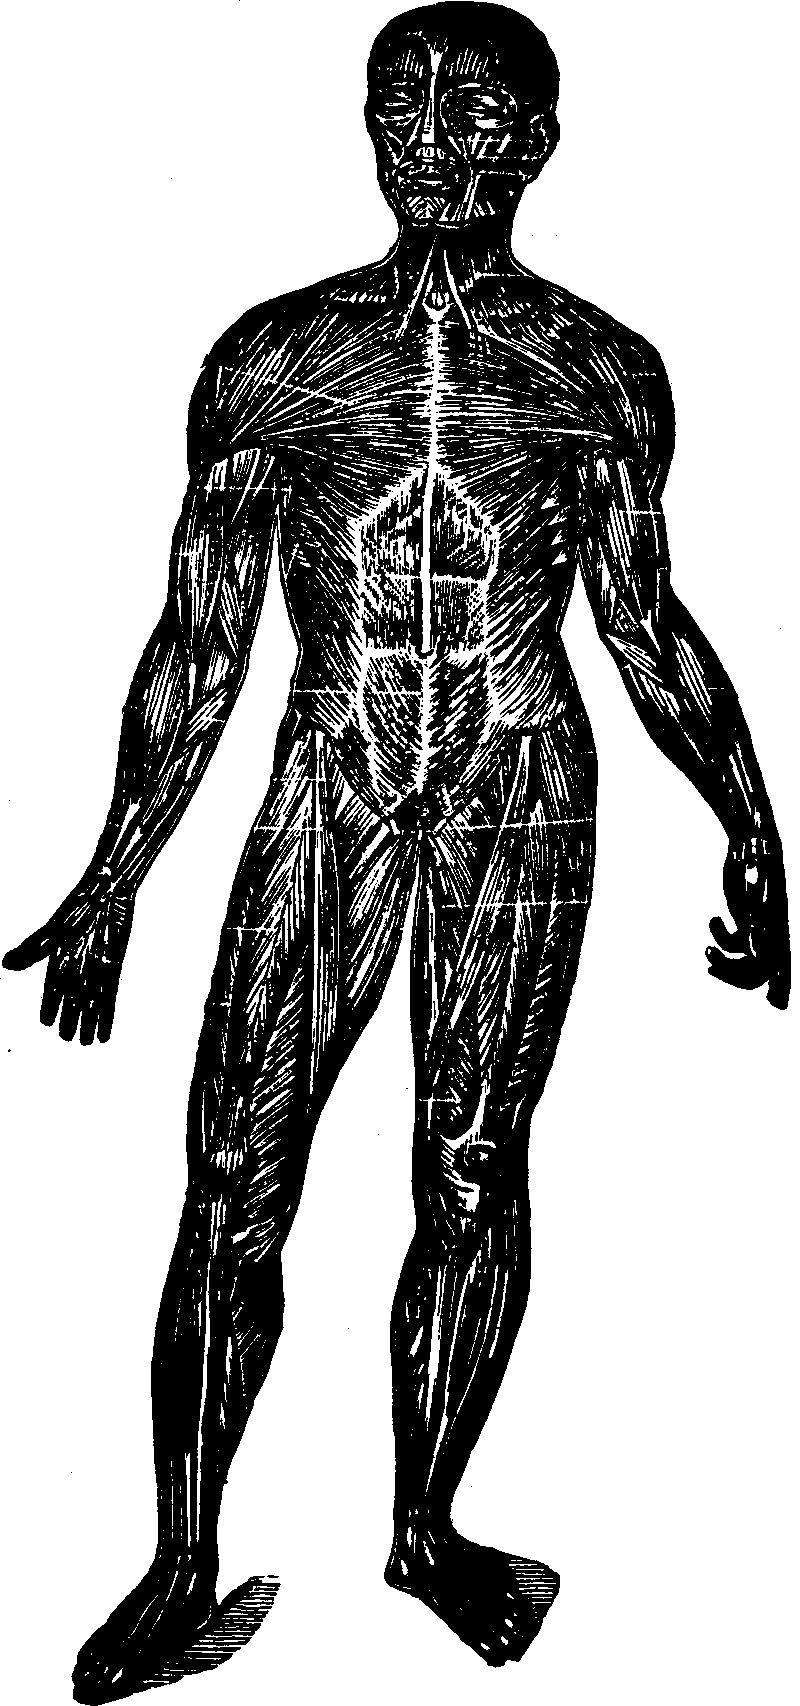

Fig.

24. A representation of the superficial layer of muscles on the anterior

portion of the body.